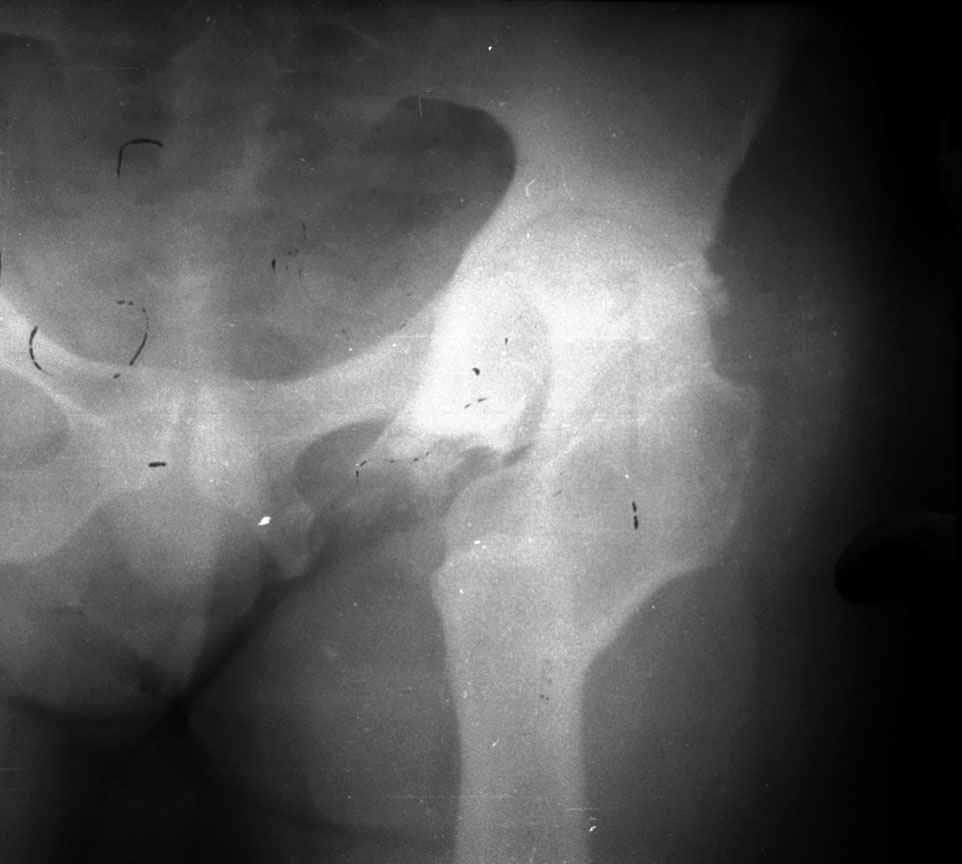

Поднят очень интересный вопрос об эффективности создания опорного бедра по Илизарову у молодых пациентов (ок). Наверное мне не повезло и я не

видел положительных результатов после этих операций, а вот проблемных больных приходится видеть достаточно часто. Причем сроки их обращения

после остеотомии короткие - 3-5 лет, а выполнение эндопротезирования после остеотомии на двух уровнях с многоплоскостной деформацией является

серьезным испытанием и для пациента и для хирурга. Я тоже не сторонник эндопротезирования в молодом возрасте, но уж после неудачных остеотомий

просто нет другого выхода. Проблема еще заключается в том, что каждый из нас видет ограниченное кол-во больных и в разные сроки. Детско-юношеские ортопеды наблюдают больных только до взрослого возраста, а дальше они

уходят из-под контроля. Современные эндопротезы дают хорошие и устойчивые результаты, поэтому не думаю, что ответ однозначный в пользу

остеотомии. Я представил Р-граммы больных с неудачными р-ми после остеотомий.

Эндопротезирование у них было на порядок сложнее в отличие от артропластики без проведения остеотомии.